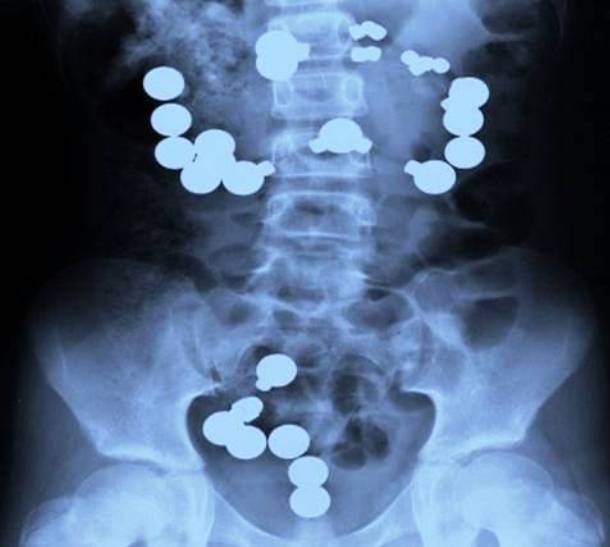

22. A Child Ingesting What She Thought Were Sweets

Shiny, round objects....sweets? This is exactly what this little girl thought as she started swallowing them. But they absolutely were not - they were magnets. And, they had to be removed quickly before they started to clump together inside her and cause major problems.Advertisement